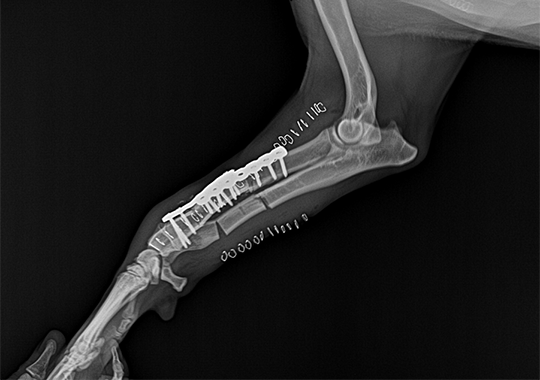

정형외과 케이스

본원은 실력 있는 전문 의료진과 최첨단 시설로 정형외과에서 좋은 예후들을 보여드리고 있습니다. 강아지에게서 쉽게 발생하는 슬개골 탈구, 십자인대 단열 뿐 아니라 다양한 고난도 케이스를 다루고 있으며, 특히 골절 수술은 회복률이 높고 타원 수술 후, 유합부전으로 본원에 내원하여 재수술에 성공한 사례가 많습니다.

요골 골절 수술 전

요골 골절 수술 후

요척골 복합만곡기형 수술 전

요척골 복합만곡기형 수술 후